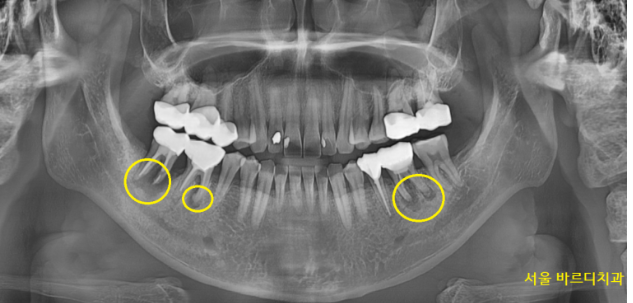

x-ray를 통해 검사부터 해보았는데요.

치아 뿌리에 염증이 있는 치아가 많았습니다.

23.12.04

문제가 있는 치아가 많지만

우선적으로 눈두덩이가 아픈 것에 집중했습니다.

눈 윗부분까지 아프다고 말씀하셨어요.

이건 전형적인 상악동염의 증상입니다.

상악동에 염증이 차고 배출이 안되면

광대뼈 주변, 눈까지 아프거든요~